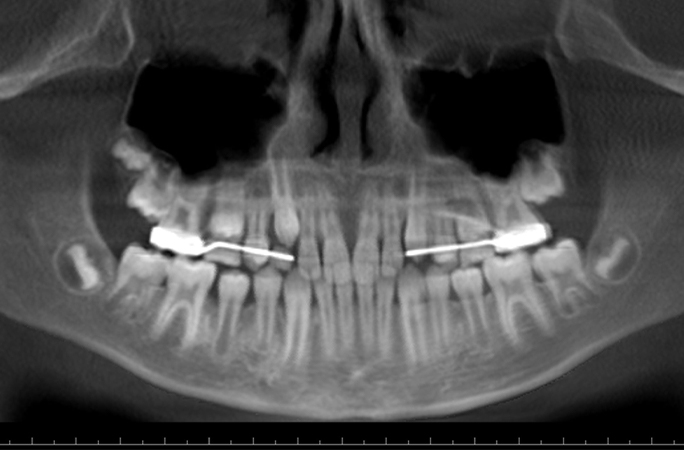

成功通過手術拔除

同年7月份,Ryan在乳齒還未完全脫落的情況下,進行了剝智慧齒手術,此時他和家人還未意識到自己即將打破健力士世界紀錄。早前並未對智慧齒有任何感覺的Ryan終於在手術中感覺到疼痛,他形容「好像被人打了一拳」,手術後吃了好幾天的流質食物才恢復正常飲食。手術後Ryan的母親才驚覺兒子成為最新的紀錄持有人,並感謝主治醫生及早發現病徵,避免了後續可能引發的其他併發症。Ryan對於殊榮也感到高興:「感覺真的很好,我很驕傲。」